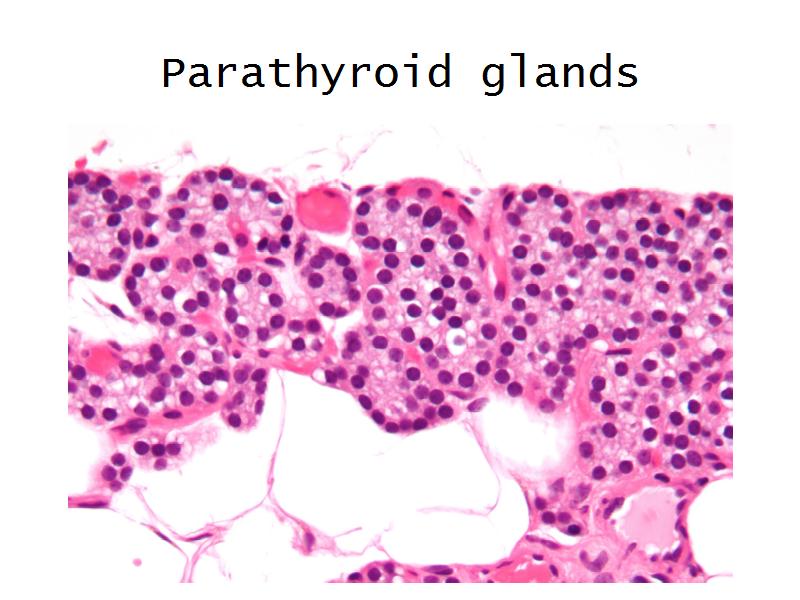

- Parathyroid glands

- E4: PTH = Chief cells in the parathyroid

- Slide 54: Parathyroid glands

Chief cells = majority

Oxyphil (acidophil) = single/groups